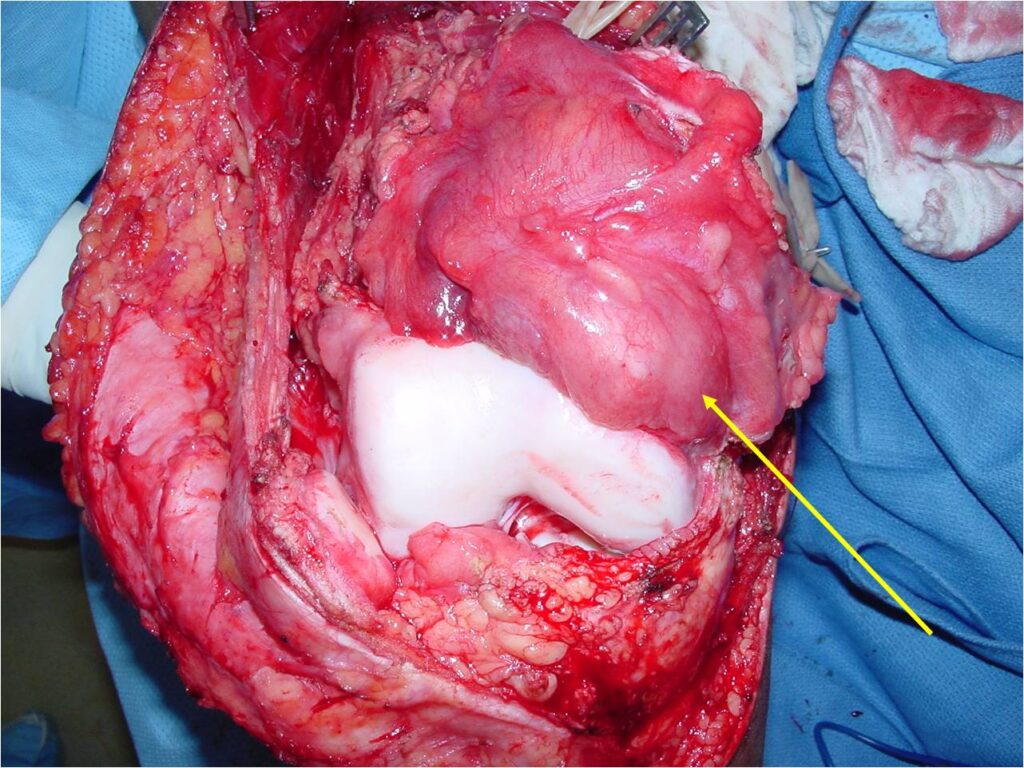

Gross Pathology

- Grossly lobulated, gray-white, translucent

- Calcification is common

- Underlying cortex eroded with irregular sclerotic reaction

- Wide Limb Sparing Resection whenever feasible